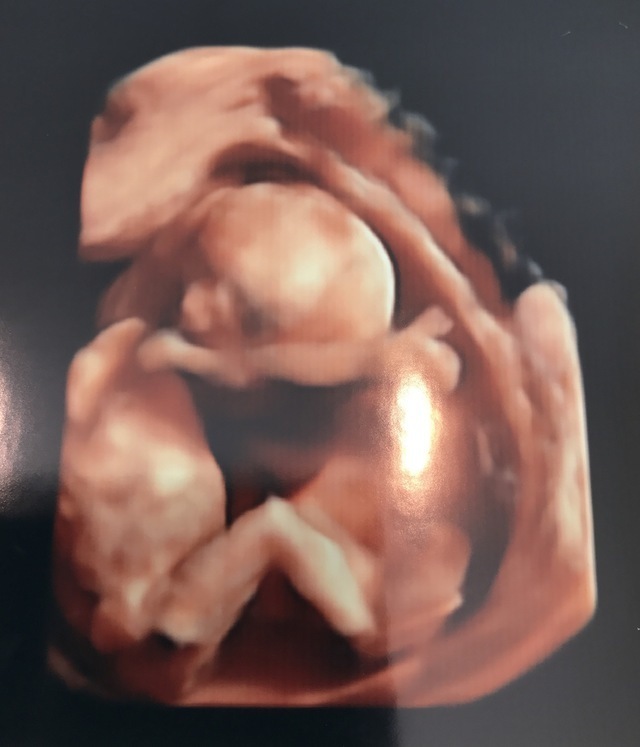

15週3日(15w3d・男の子)|kaaaa さん(25歳)

エコー写真撮影時のエピソード:

第二子にして初めて4Dエコーを貰った時のものです。まだ4ヶ月で胎動もなく今まで3Dエコーではぼんやりとした輪郭しか分からなかったのにちゃんと人の形になってる!!と感動しました。

主人も今まではエコーを見ても「ふーん」ぐらいの素っ気ない返事でしたが、これには喜んでくれました!やっぱり見やすい方が実感湧くのでしょうか。(笑)

上の子もまだ1歳でしたが、この頃から「ママのお腹には赤ちゃんがいるんだよ~~。こんなして寝んねしてるよ~~。」と話していました。毎日お腹をさすってくれて産まれる前からお姉ちゃんをしてくれています。